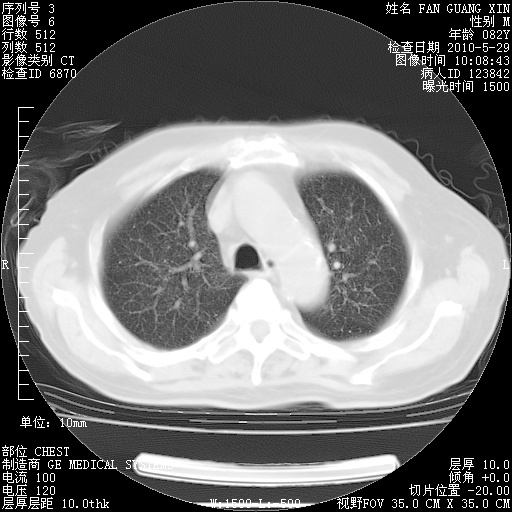

再治疗10天后的肺部CT

阅读此次胸部CT,肺间质渗出性改变较入院时有吸收。目前从体温、白细胞、中性分叶明显增高,肯定存在细菌感染(发生医院感染哦,若无消化道及泌尿系统等感染的依据,肺部感染可能大)。若你院头孢哌酮舒巴坦钠耐药率较高,同意你的方案,若48小时体温仍高,可考虑使用碳青霉稀类抗菌药物,同时可予超声雾化、注意滴数时加大液体量。白蛋白33.30g/L较低哦,需加强营养等支持治疗。